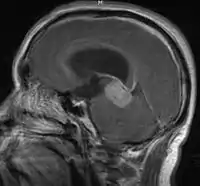

- Mainly located in midline structures, suprasellar region or pineal gland, also basal ganglia and hypothalamus

- Pineal Gland Germinoma

- Suprasellar Germinoma

- Toronto; 2006 (1995-2004) PMID 16530340 -- "Limited-field radiation for bifocal germinoma." (Lafay-Cousin L, Int J Radiat Oncol Biol Phys. 2006 Jun 1;65(2):486-92.)

- Retrospective. 6 patients with bifocal germinoma (pineal + suprasellar). All with diabetes insipidus at presentation. Treated with chemo followed by limited-field RT (whole ventricle 24-40 Gy +/- boost). Median F/U 4 years